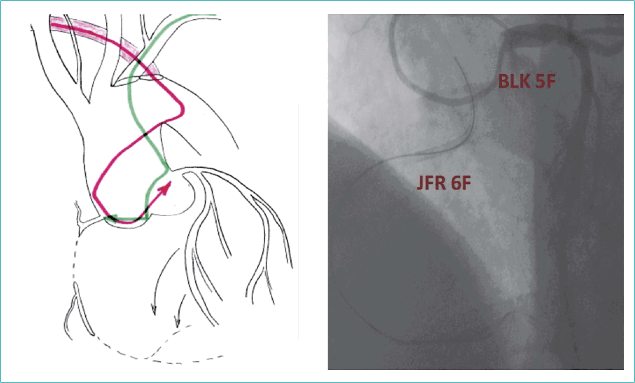

Наиболее удобным оказался JFR 6F Adroit (Cordis). При его адекватной поддержке удалось реканализировать ПКА, используя коронарный проводник Gaia Third (ASAHI). Для определения положения проводника в дистальной части ПКА выполнялось контрастирование из системы ЛКА. Для этого через правую лучевую артерию (через a. l.) был заведен диагностический катетер BLK 5F (TERUMO) и успешно катетеризировано устье ствола ЛКА (рис. 6).

Рисунок 6. Схема и ангиографическая картина катетеризации правой и левой коронарных артерий

Figure 6. Scheme and angiographic picture of the catheterisation of the right and left coronary arteries

После реканализации ПКА имплантированы стенты с антипролиферативным покрытием с хорошим непосредственным ангиографическим результатом (рис. 7).

Рисунок 7. Контрольная ангиография после стентирования правой коронарной артерии

Figure 7. Control angiography after the right coronary artery stenting